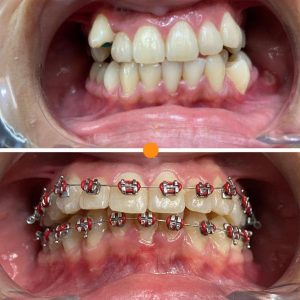

Tratamientos Ortodoncia Blanqueamiento dental Zoom Contacto 72 2795 9597 Marcar Ahora Envia whatsapp Visita nuestro facebook